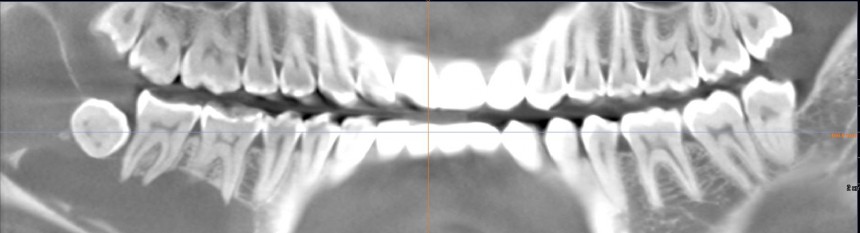

Примерно полтора года назад к нам в клинику обратилась молодая и красивая девушка. Все бы ничего, ничто ее не беспокоило, но вот однажды пошла она лечить зубки, и ей сделали панорамный снимок. Сделали панорамный снимок — забегали, заохали, послали на компьютерную томографию. Вот она:

или вот:

Для тех, кто не разбирается в компьютерной томографии, я поясняю:

Как видите, большую часть тела и ветви нижней челюсти справа занимает гигантская фолликулярная киста. Она образовалась из-за ретинированного зуба мудрости #48. Дело в том, что вокруг ретинированных зубов мудрости сохраняется фолликул, оболочка зачатка зуба. И в определенных условиях (каких — науке пока неизвестно) клетки фолликула могут пойти в рост — он постепенно вытесняет костную ткань и формирует гигантские кисты, которые называются фолликулярными.

Причем, эти кисты могут существовать длительное время без каких-либо внешних симптомов. И обнаруживаться случайно, либо на рентгенограмме (если пациент пришел лечить зубы), либо в тот момент, когда во время зевания или малейшей жевательной нагрузки челюсть ррраз! — и ломается. Последнее, согласитесь, — очень неприятная штука.